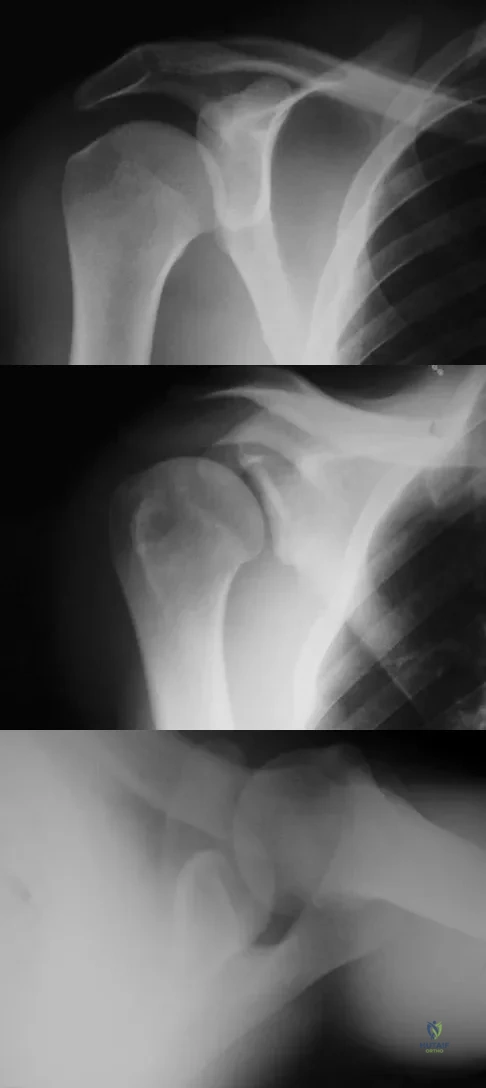

A 21-year-old patient has had pain and a marked decrease in active and passive shoulder motion after having had a seizure 2 months ago as the result of alcohol abuse. Current AP and axillary radiographs and a CT scan are shown in Figures 26a through 26c. Management should consist of

Detailed Explanation